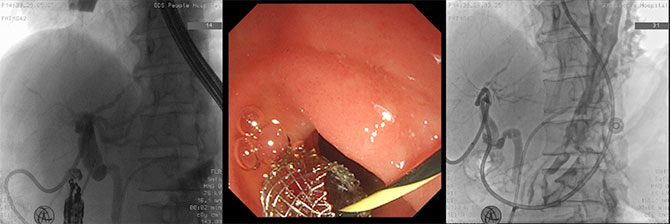

61岁的王先生(化名),肝移植1年后,胆管接口处发生狭窄,再次出现严重黄疸。外院的经肝胆道引流效果不佳,且因结构改变,常规ERCP失败。更危急的是,他很快出现了严重感染和急性梗阻性化脓性胆管炎伴休克,拟行超声内镜下肝胃吻合术(EUS-BD-HGS),也就是在肝内胆管和胃之间放置一个支架,使淤积的胆汁通过支架流向胃内并排出,这也是ERCP失败后首选的EUS-BD术式之一。但是术中发现肝内胆管扩张不明显。

患者转到我院,在胰腺中心陈汝福主任、余敏副主任医师的支持下,经胰腺中心和内镜中心联合评估后,果断选择EUS-BD-CDS。在麻醉科张光燕医生的精细配合下顺利完成。堵塞的胆道瞬间恢复通畅。王先生的感染和休克风险因素迅速解除,重新看到了生命的曙光!

超声内镜下胆总管-十二指肠吻合术